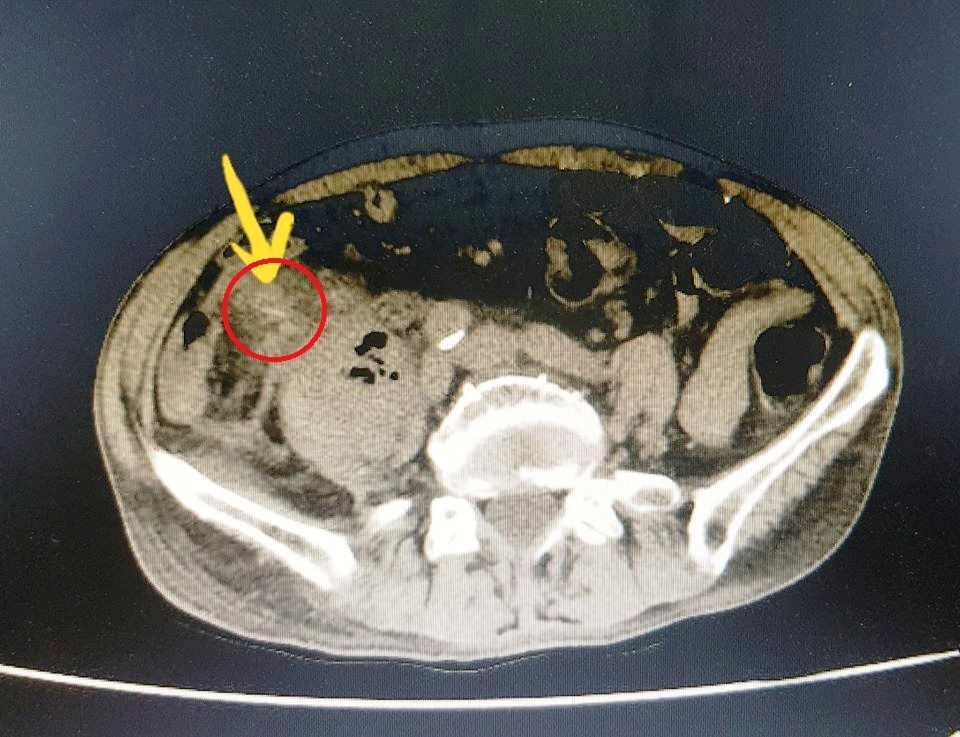

Kết quả CT Scan cho thấy có hình ảnh tụ dịch khí vùng ngực trung thất, với dị vật nhọn cản quang ngay sát cung động mạch chủ.

Ngay lập tức, các bác sĩ nhận định đây là ca bệnh nặng, nguy cơ tử vong cao hoặc có thể bị di chứng nặng nề sau mổ vì mảnh xương nhọn lâu ngày gây áp xe nhiễm trùng hoại tử vùng lồng ngực, thậm chí gây thủng động mạch chủ ngực.